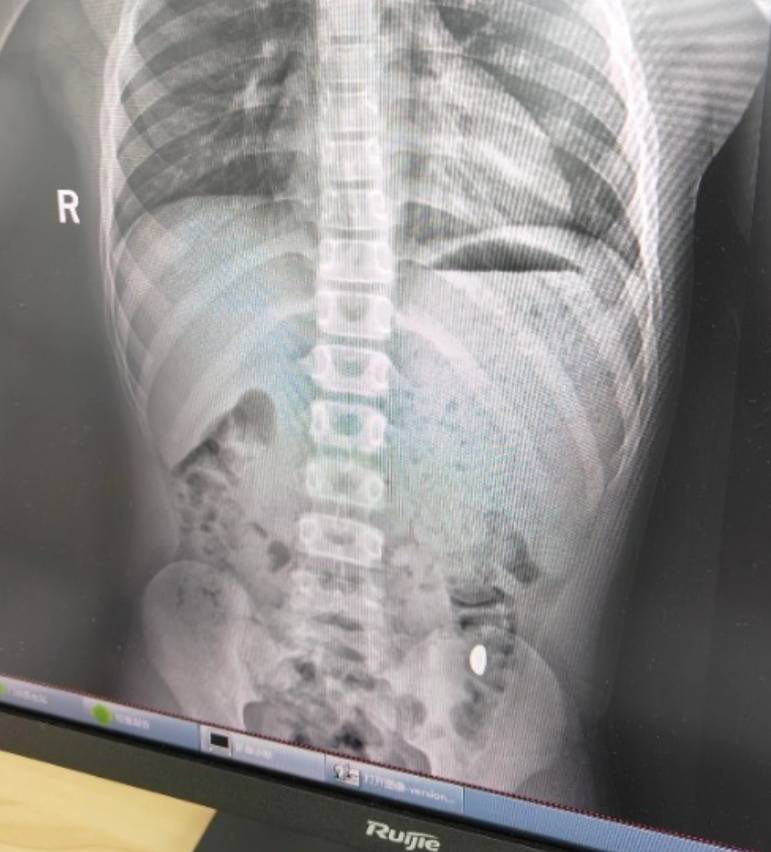

右下加亮点为金豆。